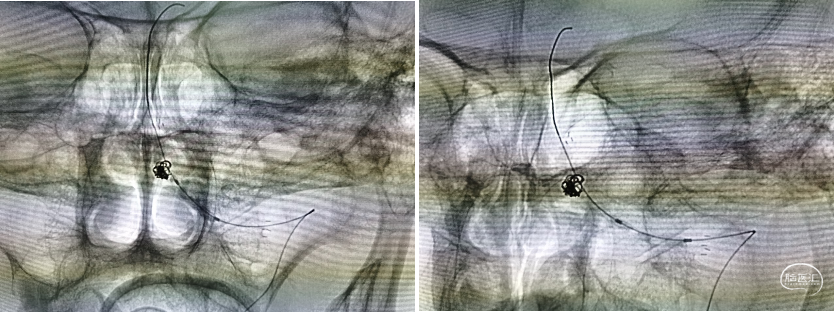

三型弓,最终采用泥鳅导丝、4F MPA1、6F Envoy同轴技术送入左侧椎动脉

造影提示右侧椎动脉闭塞,左侧椎动脉V4多发重度狭窄,并V4段夹层动脉瘤

Transcend携带SL-10微导丝进入左侧大脑后动脉,明确真腔内后交换Gateway2.0mm×15mm以命名压缓慢进行两次扩张,造影见现在较前改善,动脉瘤近端存在狭窄暂时未扩张